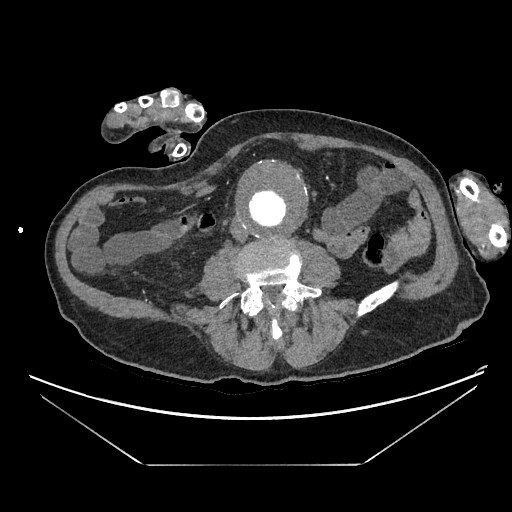

Destaca la visualización de probable litiasis renal derecha, junto con el hallazgo incidental de aneurisma de aorta abdominal, de unos 5,8 cm de diámetro máximo en el plano axial, el cual presenta trombo mural.

Dados los hallazgos, se completa estudio con AngioTC, confirmando la existencia de aneurisma infrarrenal de 6 mm de diámetro mayor, junto con litiasis renal derecha de 5,5 mm y dilatación de la pelvis renal.